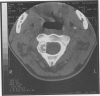

Osteoblastoma is a benign bone-forming tumor that represents approximately 1% of all primary bone tumors. It occurs 40% of the time in the spine, most commonly in the posterior elements. The clinical presentation in this case is of chronic neck pain and stiffness. Although most lesions are well visualized on plain films, a bone scan or CT scan may be of better diagnostic value. Treatment is via surgical excision. In this report we present a case of cervical osteoblastoma mistaken for mechanical neck pain.

Images in this article